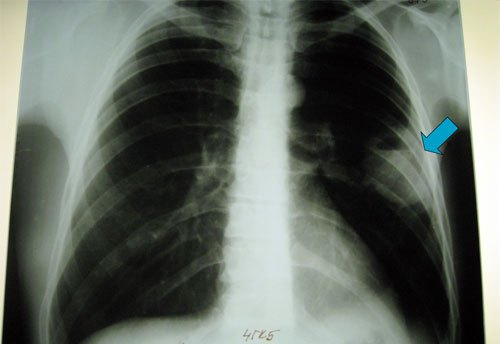

- рентгенография грудины;

Рентгенограмма левосторонней пневмонии

- Рентгенографическое исследование органов грудной клетки. На рентгене пораженный сегмент выглядит затемненным или, при позднем этапе течения болезни, чрезмерно осветленным.